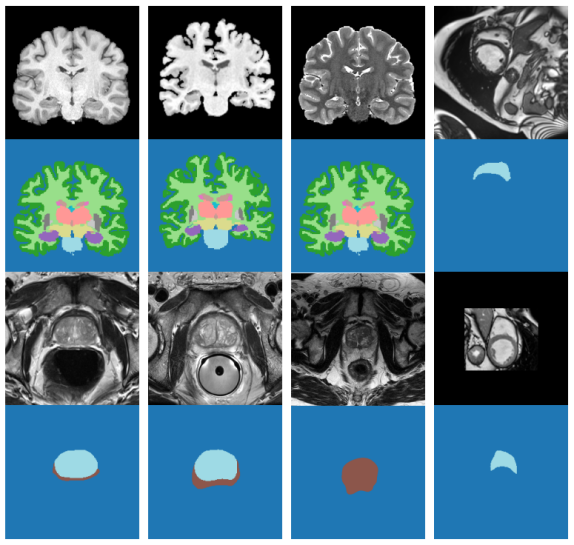

Fig. 2 shows some images from the different datasets and their corresponding segmentations. Note that, for each anatomy, the underlying segmentations are very similar across domains, while the image contrasts vary. Table 1 shows our training, test and validation split (in terms of number of 3D images) for each dataset.